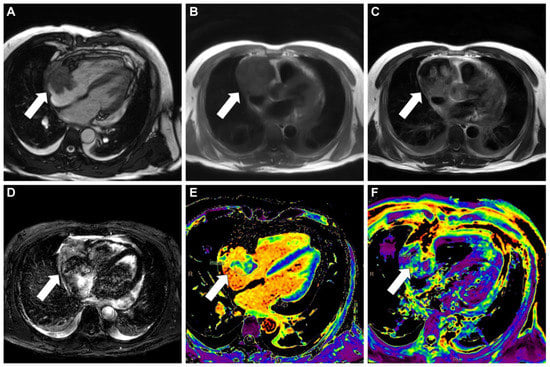

Figure 1. Initial evaluation using transthoracic echocardiography demonstrated a preserved ejection fraction of the left ventricle, a dilated right ventricle with a moderate degree of tricuspid regurgitation (A), and mild tricuspid stenosis on color Doppler, in addition to a significant amount of pericardial effusion, measuring 23 mm at the apex. The patient underwent pericardiocentesis to alleviate the symptoms. Approximately 200 mL of sanguineous fluid was extracted from the catheter, and microbiological and cytological examinations were negative for infection or malignancy. Subsequent transesophageal echocardiography revealed a hyperechoic mass in the right atrium. The mass protruded through the tricuspid valve and deeply penetrated the posterior wall of the right atrium (B). Further investigation using cardiac computed tomography with contrast enhancement confirmed the presence of a large mass (white arrow)in the right atrium sized 42 mm × 35 mm in the axial plane (C) and inhomogeneous central enhancement in the delayed phase, indicating a vascular mass (white arrow) with hemopericardium (D).

Diagnostics 13 02666 g001